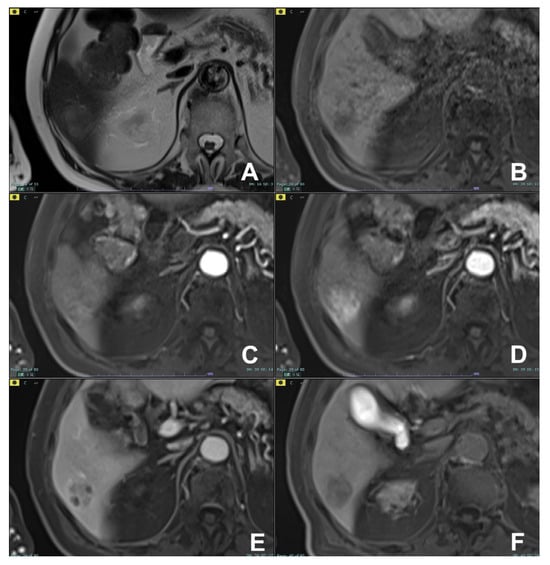

| Differential diagnosis pancreatic cancer (PC) from mass forming pancreatitis (e.g., paraduodenal pancreatitis-PDP, autoimmune pancreatitis-AIP) | HASTE T2 | AXIAL | -- | Anatomy and liquids analysis |

| Indications: The use of multiparametric imaging (DWI, contrast enhanced) allows one to differentiate with substantial accuracy a mass forming pancreatis from a pancreatic carcinoma. | HASTE T2 | CORONAL | -- | Anatomy and liquids analysis |

| GRE T1 FS | AXIAL | -- | Pancreatic parenchima assessment | |

| DWI b 0–50–400–800 | AXIAL | -- | Restricted diffusion most likely to be PC or AIP | |

| GRE T1 3D DYNAMIC | AXIAL | Pre- 25″–70″–180″ | PC is most likely hypovascular; mass forming pancreatitis usually shows delayed homogeneous enhancement | |

| MRCP 3D/2D | OBLIQUE CORONAL | Anatomy of wirsung duct | ||

| MRCP 2D with secretin | OBLIQUE CORONAL | For the differential diagnosis of pancreatic duct stenosis (“duct penetrating sign”) | ||